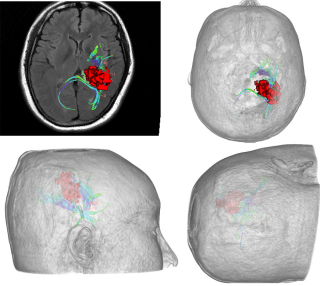

对于神经外科医生而言,三维可视化技术复现手术场景是较为直接的技术提高路径。通过三维可视化技术可以实现手术路径模拟,体位摆放模拟,多模态三维可视化技术整合到虚拟现实和增强现实应用之中,可有效提高术者对于术中情况的判断。

我们把一些前期工作与这里同事分享交流共同提高。也希望能够建立起具有高原特色的三维可视化模拟手术实验室,为这里的医疗工作增色添彩。